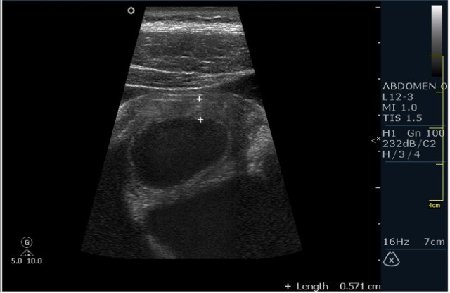

Мужчина 42 года; жалобы на периодические боли в эпигастрии. УЗИ области жёлчного пузыря выявило интересную картину; наблюдается фокальное утолщение стенок пузыря в области тела. Интересно узнать Ваше мнение?

В Желчном пузыре определялся мелкий конкремент и диффузное равномерное гипоэхогенное утолщение стенки на отграниченном участке, заключение морфологов-воспaлительный процесс (признаки холецистита).

Мне интерено, а почему Вы решили что это аденомиоматоз? На представленных сонограммах нет признаков этого заболевания, за исключением фокального утолщения стенки (что крайне не специфично, см. ниже). Если мы не находим пристеночных синусов (Ашоф -Ракитанского) образующихся за счёт неравномерной гиперплазии эпителия ЖП с протрузией эпителия в стенку, и не видим гиперэхогенные фокусы в стенке за счёт кристаллов холестерола; мы не можем выставлять диагноз аденомиоматоз. В нашем случае мы имеем дело с равномерным гипоэхогенным утолщением (см. сонограммы призведённые линейным датчиком с высоким разрешением).